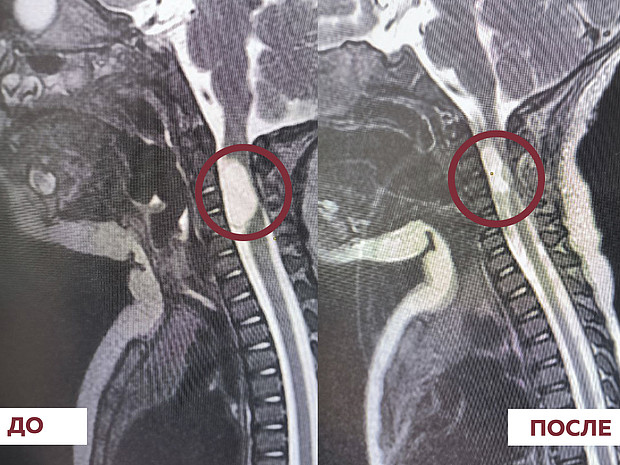

Внедрить в работу учреждения новые высокотехнологичные виды операций помог национальный проект «Здравоохранение»